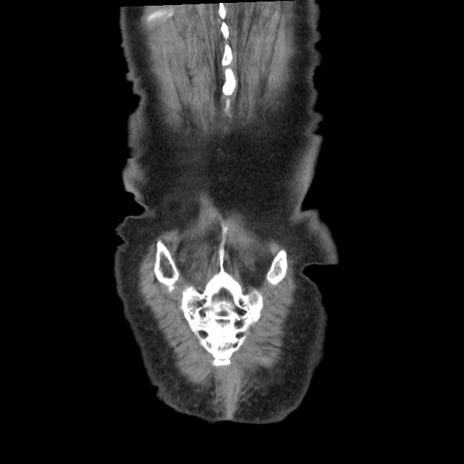

症例1(冠状断像)

矢状断像